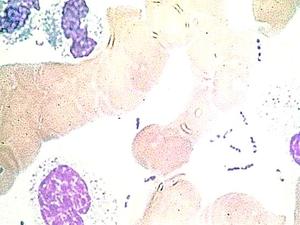

Hallan la cepa más antigua de la bacteria de la peste negra